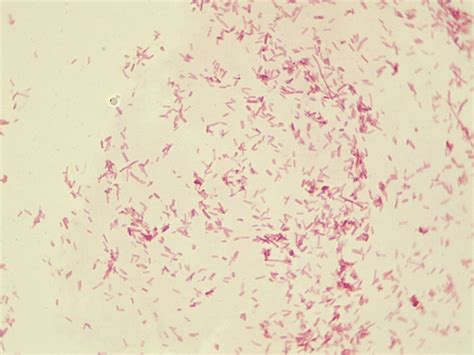

Exploring the microscopic world of bacteria can be both fascinating and educational. One of the most commonly studied bacteria under the microscope is *Escherichia coli*, often abbreviated as *E. coli*. This bacterium is a gram-negative, rod-shaped organism that is part of the normal flora of the human gut. Understanding *Escherichia coli under microscope* provides valuable insights into its structure, behavior, and potential roles in health and disease.

When observed *Escherichia coli under microscope*, several key morphological features become apparent. *E. coli* is a rod-shaped bacterium, typically measuring about 2.0 µm in length and 0.25-1.0 µm in diameter. Its gram-negative nature means it has a thin peptidoglycan layer and an outer membrane, which can be visualized using specific staining techniques. The bacterium's flagella, which are used for motility, are also visible under high magnification.

• Gram Staining: This technique differentiates between gram-positive and gram-negative bacteria. *E. coli*, being gram-negative, will appear pink or red under the microscope.